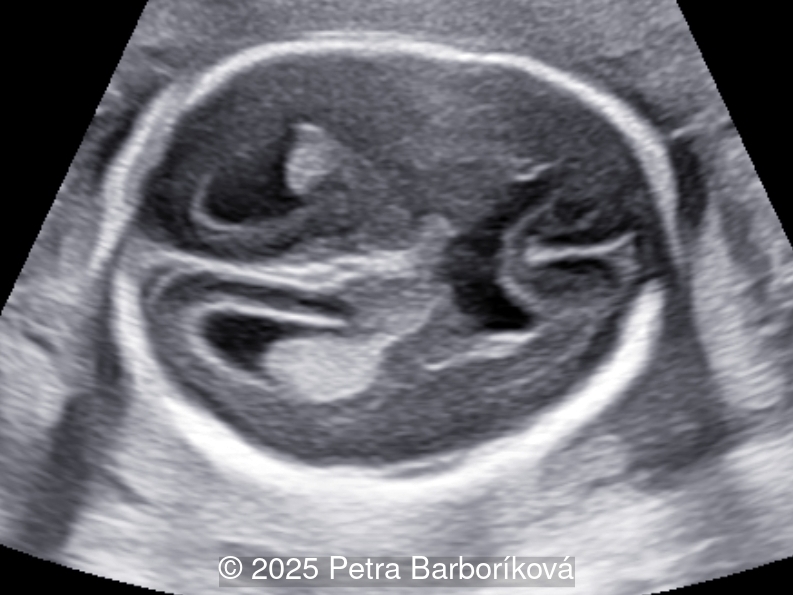

We present a case of agenesis of the cavum septum pellucidum (CSP).

At 20 weeks, detailed ultrasound under conditions of severe oligohydramnios demonstrated absence of the typical box-shaped anechoic structure of the cavum septum pellucidum (CSP). The frontal horns of the lateral ventricles appeared narrow and pointed, giving the characteristic “bull’s horns sign.” Multiplanar and 3D reconstructions confirmed the presence of the corpus callosum, while the CSP was absent. Other midline and posterior fossa structures appeared normal. The optic chiasm was partially visualized, although assessment was limited by technical conditions. Fetal magnetic resonance imaging (MRI) was subsequently performed and confirmed isolated agenesis of the CSP with preserved corpus callosum and posterior fossa structures. The optic chiasm and pituitary stalk are visible in the sellar region, but the pituitary gland itself is not clearly identified in the sella turcica as it is a very small structure. No additional central nervous system anomalies were detected.